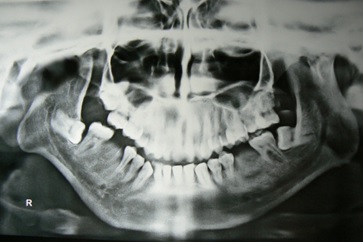

Total 10 patients with Temporomandibular Joint (TMJ) ankylosis reporting to the outpatient department of Oral and Maxillofacial Surgery, Maharaja Ganga Singh Dental College and Research Centre, Sri ganganagar, Rajasthan, India were included irrespective of age, sex, caste and socioeconomical status. Diagnosis of TMJ ankylosis was based on the basis of clinical assessment as Maximum inter-incisal Mouth Opening (MMO) [Table/Fig-1] and other cardinal signs of ankylosis [1] followed by radiographic assessment using Postero-anterior (PA) mandible view, Orthopantomogram (OPG), lateral oblique view and CT scan which showed various degrees of condylar involvement with condyles varying from normal size to a large spherical mass involving the condylar process as well as the coronoid process [Table/Fig-2].

Results: A total of 10 patients with TMJ ankylosis were successfully treated by interpositional gap arthroplasty. Mean age of the patients was 8.6 years. All the patients had a history of trauma to the TMJ which could be the aetiological factor for TMJ ankylosis. Patients had pre-operative maximal mouth opening at incisal edges of 1-11mm, (mean 6.8mm). Patients had maximum mouth opening of 30-38mm (mean 34.5mm) on last follow-up (mean 4.1 years). Transient paraesthesia of the temporal branch of facial nerve was observed in 1 case which was recovered within 3 months by conservative treatment. Periodic OPGs were obtained to check the maintenance of the intra-articular space [Table/Fig-10]. There were no signs of recurrence in any patients up to last follow-up visit [Table/Fig-11]. Overall results of all the cases have been described in [Table/Fig-12].

Post-operative X-rays show no signs of recurrence.